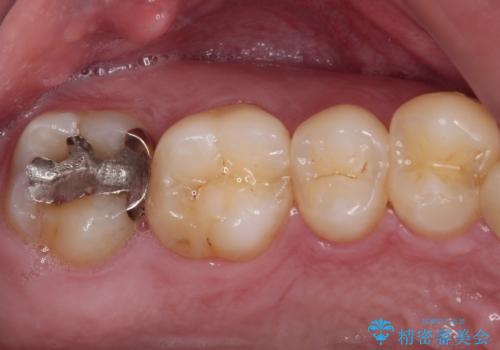

- 近医にて、銀歯の周りの歯が欠けてむし歯のようになっていると言われたとのことで来院された患者様です。

非常に咬合力が強く、銀歯やセラミックのような堅い素材では歯にダメージがかかり、治療を繰り返す可能性が高いと思われたので、ゴールドインレー(白金加金インレー、PGAインレー)にて、治療中の歯と銀歯が装着されている歯を修復治療することとしました。